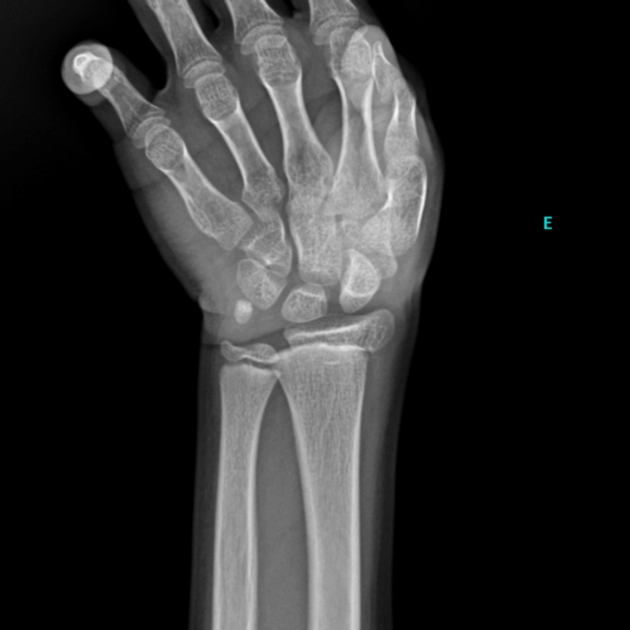

• Cơ xương khớp

• Bệnh lý cơ xương khớp ở thanh thiếu niên

Gãy sụn tiếp hợp (Gãy Salter-Harris)

16/03/2026